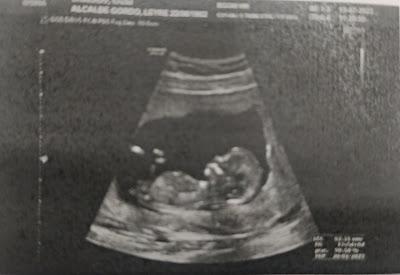

A finales de noviembre tuve la ecografía del tercer trimestre y aquí fue donde vino el susto, pues la cabeza salió un poco más pequeña que el resto del cuerpo y tuve que hacerme una resonancia fetal. El problema es que tuve que esperar tres semanas y la incertidumbre fue terrible. Y eso que intentaba no pensarlo mucho, porque cada vez que lo hacía se me saltan las lágrimas. Intentaba no agobiarme pensando que con África pasó lo mismo (siempre salía la cabeza un poco más pequeña), pero con ella no tuve que hacerme la resonancia y eso era lo que mas me inquietaba. Finamente el 19 de diciembre me hice la resonancia y al día siguiente me dieron los resultados diciendo que estaba todo bien. No os imagináis lo que lloré (todo lo que me aguanté las semanas anteriores). La rabia fue que al día siguiente tuve revisión de control de crecimiento del feto y con los nervios se me olvidó recordar que no queríamos saber el sexo del bebé, por lo que se les escapó y (otra vez, con África pasó igual) supimos que era una niña.